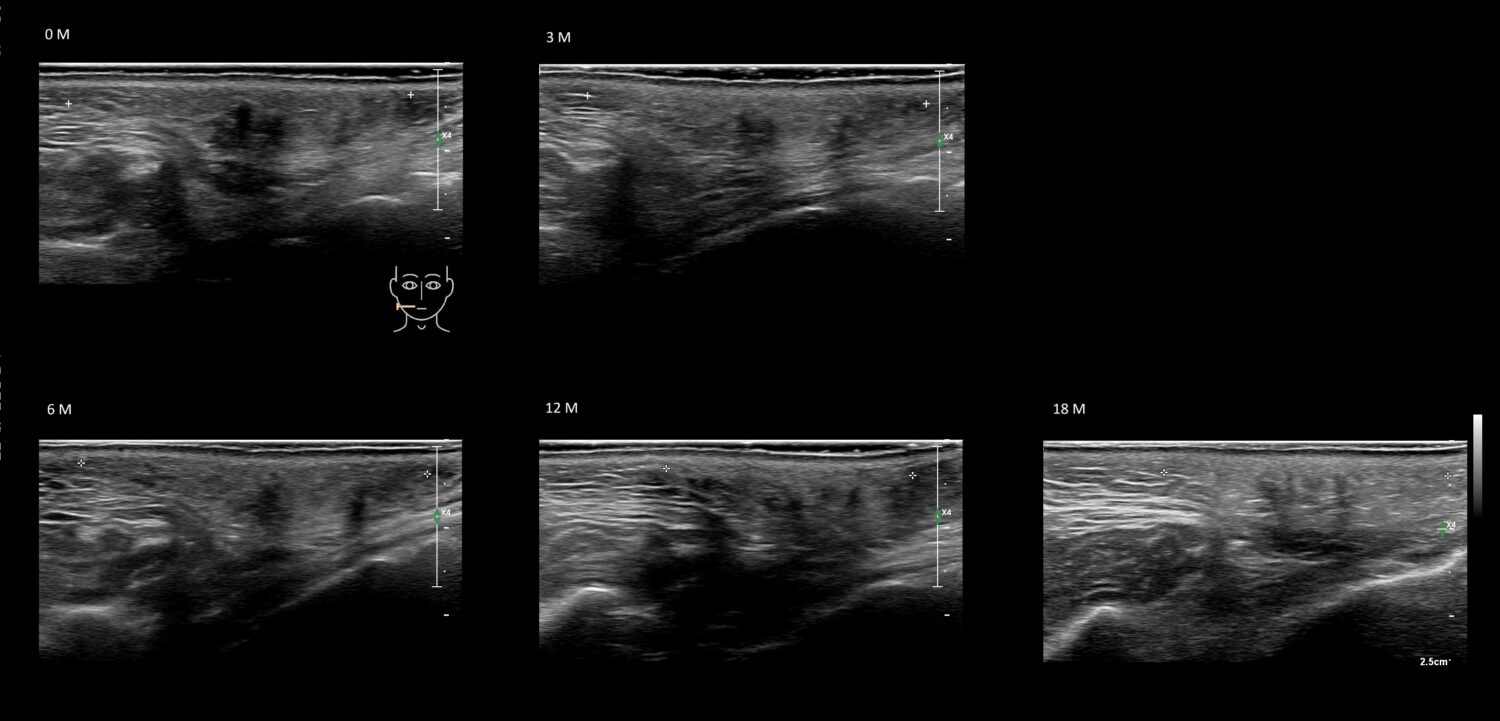

Draw in the second image below where the fillers are located. To check if your answer is correct, swipe the first image to the right.